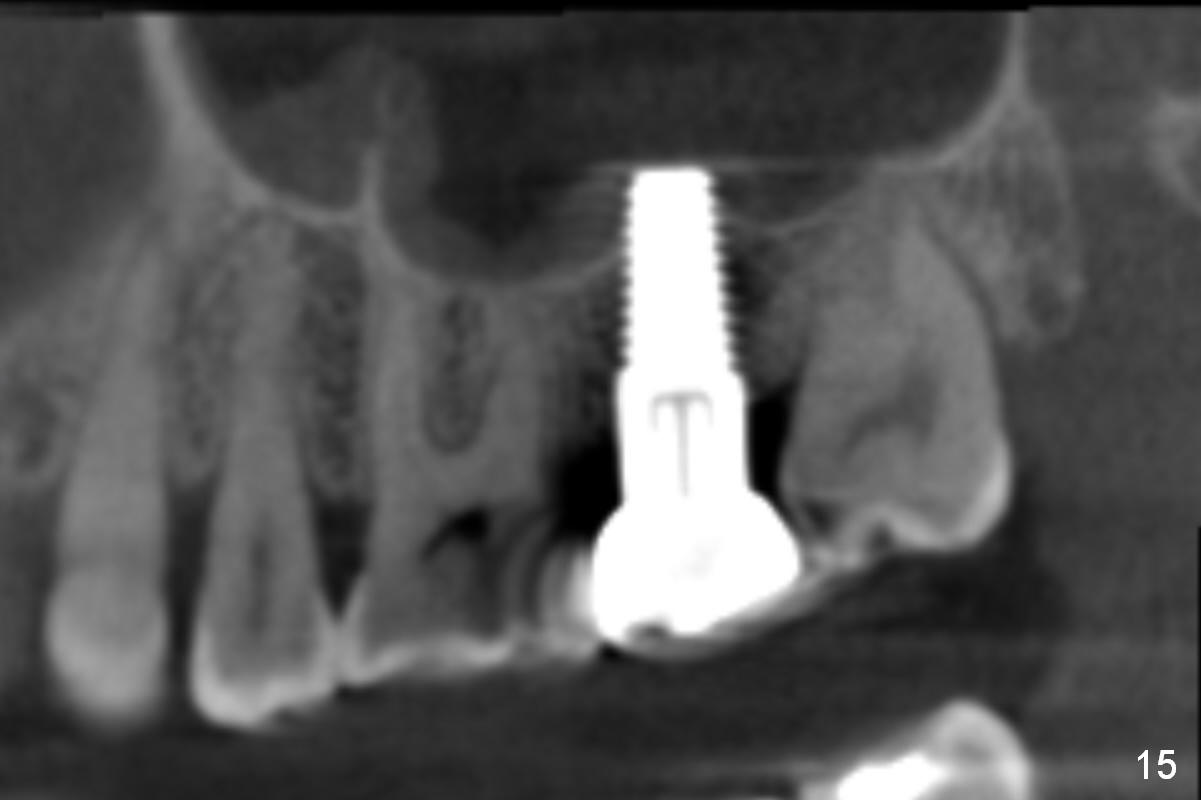

A 42-year-old man is afraid of dentistry. Residual roots of #2 remain untreated for at least 2.5 years (Fig.1). Both the mesiodistal space and the height are limited and unfavorable to restoration (Fig.2,3). Finally he agrees to have treatment, since the tooth #15 is worn so much that it is sensitive to mastication. When the tooth #2 is extracted, the socket is triangular without septum (Fig.4); the bottom of the socket is flat and easy for osteotomy. A 5x17 mm tap has obtained stability once it is placed ~ 14 mm deep (Fig.5). A 5x14 mm implant is placed with insertion torque > 60 Ncm (Fig.6 I), followed by placement of 4x3 mm abutment (A).

CBCT taken 23 months post cementation shows no abnormality (Fig.15-17). On the contralateral side, the apex of the tooth #15 is immediately inferior to the sinus floor (Fig.18 (sagittal section), 19 (coronal section)). The immediate implant seems to be unavoidably entering the sinus. The implant seems to be normal 3 year 5 months post cementation.